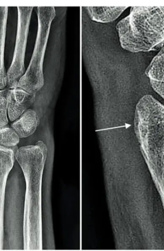

И опять у невролога возникли сомнения относительно верности интерпретации исследования, в связи с чем врач обратился к врачу МРТ с диском. И опять не зря! По снимкам выявлено выраженное повреждение сухожилий передней большеберцовой и длинной малоберцовой мышц, что и прояснило причину нарушения движений в левой стопе. На рисунке стрелками указаны поврежденные сухожилия — вначале целые, потом разрыв, затем вновь нормальная структура.